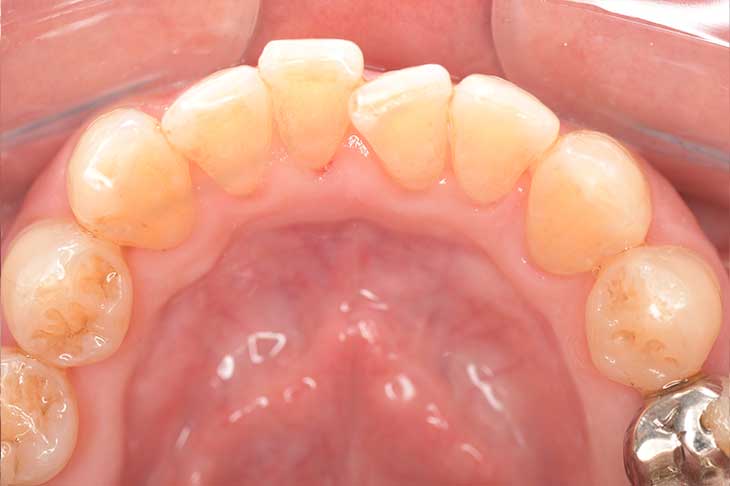

CASE 14

下顎before

下顎after

臼歯before

臼歯after

基本情報

| 年齢・性別 | 27歳・男性 |

|---|---|

| 主訴 | 歯石とりたい |

| 治療内容 | スケーリング |

| 治療期間 | 30分 |

| 治療費 | 約1,500円(保険診療) |

| リスク・副作用 | 知覚過敏、歯肉退縮、出血 |

| 治療方針 | 歯列不正でプラークがつきやすいため、TBIを行い定期的に歯石を除去していきます。 プラークコントロールが出来るようになったら定期検診でクリーニングを行っていきます。 |